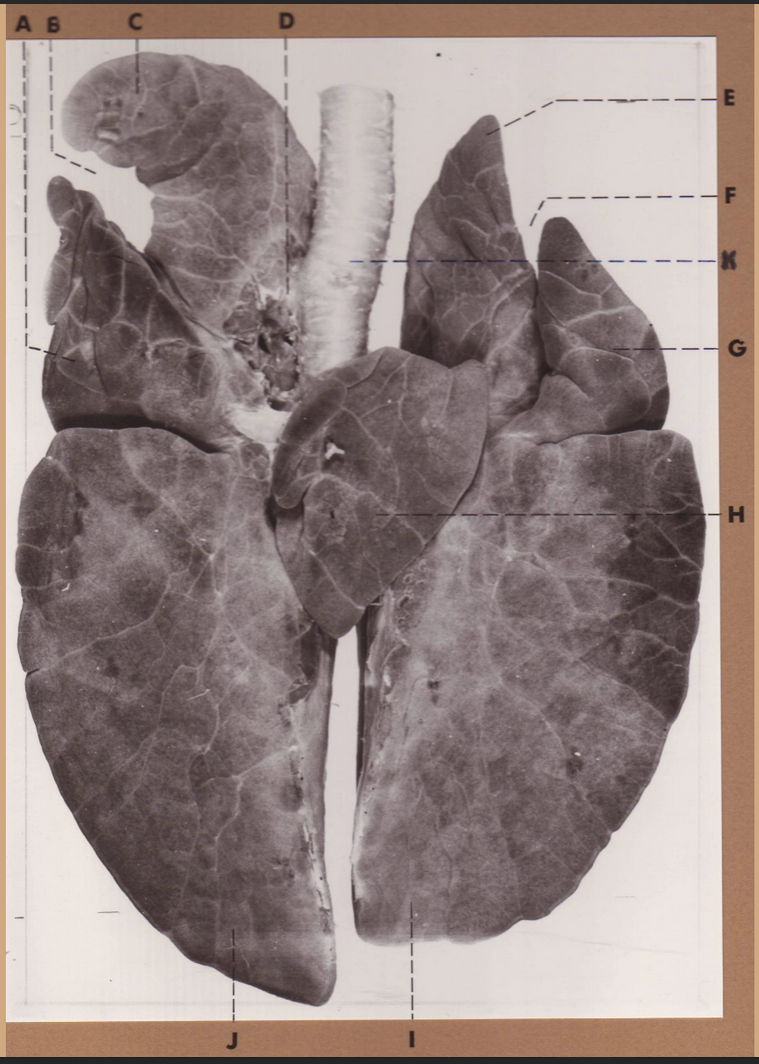

A

(pig lungs, dorsal)

L cranial lobe, caudal segment

B

(pig lungs, dorsal)

L cranial lobe, cranial segment

C

(pig lungs, dorsal)

trachea

D

(pig lungs, dorsal)

R cranial lobe

E

(pig lungs, dorsal)

cardiac notch

F

(pig lungs, dorsal)

middle lobe

G

(pig lungs, dorsal)

dorsal border

H

(pig lungs, dorsal)

costal surface

I

(pig lungs, dorsal)

basal border

J

(pig lungs, dorsal)

R caudal lobe

K

(pig lungs, dorsal)

L caudal lobe

A

(pig lungs, dorsal)

L cranial lobe, caudal segment

B

(pig lungs, dorsal)

L cranial lobe, cranial segment

C

(pig lungs, dorsal)

trachea

D

(pig lungs, dorsal)

R cranial lobe

E

(pig lungs, dorsal)

cardiac notch

F

(pig lungs, dorsal)

middle lobe

G

(pig lungs, dorsal)

dorsal border

H

(pig lungs, dorsal)

costal surface

I

(pig lungs, dorsal)

basal border

J

(pig lungs, dorsal)

R caudal lobe

K

(pig lungs, dorsal)

L caudal lobe